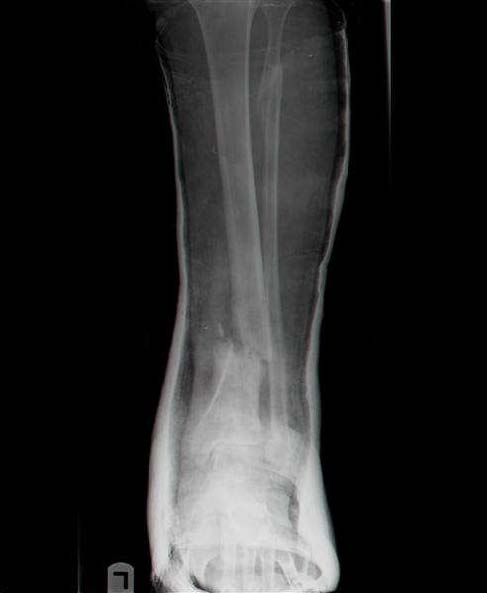

Женщина 46 лет, неудачно лечившаяся по поводу перелома голени в нижней 1\3 сначала в гипсе, поступила через 6 месяцев после остеосинтеза пластиной (рис 1). Имелась деформация в нижней 1\3 голени: варус, антекурвация, наружная ротация, два свища. Удалена пластина, дебридмент мягких тканей,

остеотомия м\б кости, аппарат Илизарова. По рентгенограммам в двух проекциях произведено планирование устранения смещений (рис 2 и 3), между вторым и третьим кольцом установлены 6 телескопических дистракторов Гесапода, данные введены в программу, и далее втечение 10 дней больная подкручивала телескопы согласно выданной компьютером инструкции. По завершению репозиции гексаподные телескопы обратно заменены на обычные штанги от аппарата Илизарова (рис 4 и 5). Еще через две недели забит гвоздь (рис 6, контроль

через 4 месяца).